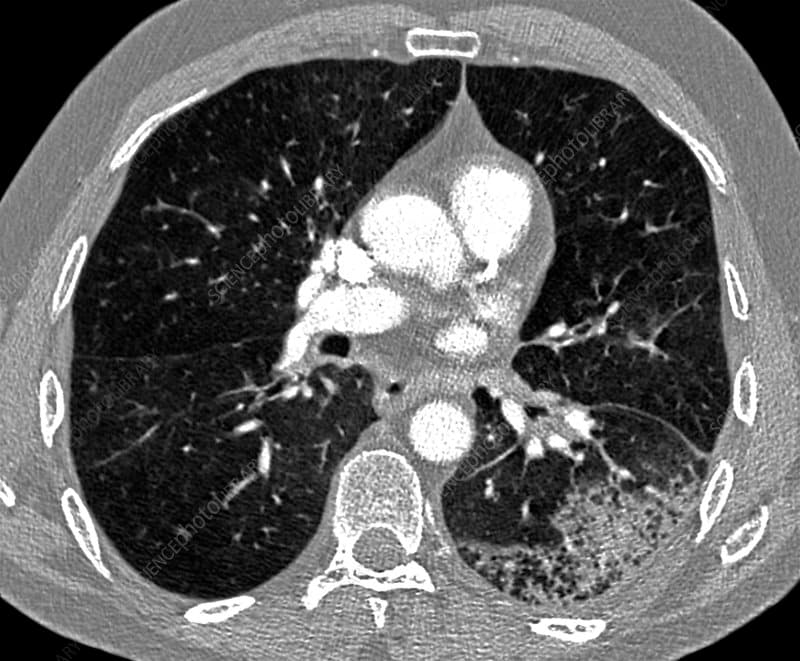

Pneumonia is an infection of the lungs that ranges from mild to life-threatening. Learn the common causes, warning signs, how it’s diagnosed and treated, and practical prevention tips including vaccines.